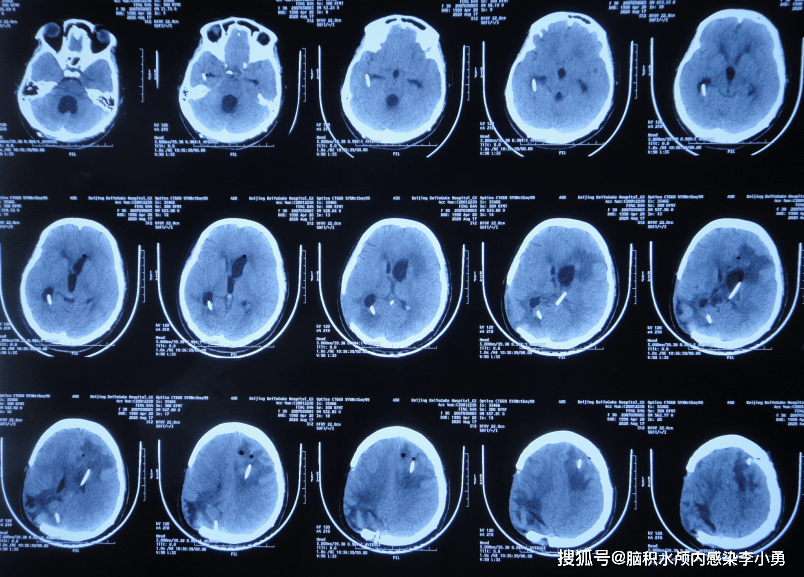

2020年8月17日入院治疗54天即2020年8月29日,查头颅ct侧脑室,第四脑室

在山西省某三甲医院复查,头颅ct提示"梗阻性脑积水,侧脑室,三脑室增大